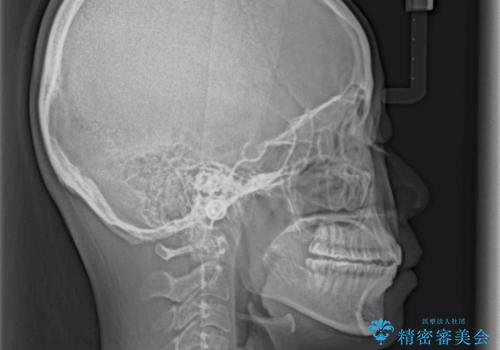

上の前歯が下の前歯を乗り越える際、奥歯がほとんど咬めない時期があり、乗り越えた後も、インビザライン特有の奥歯の咬みにくさが続きました。

咬み合わせ改善のために治療期間を要しましたが、最終的に奥歯はしっかりと咬めるようになりました。